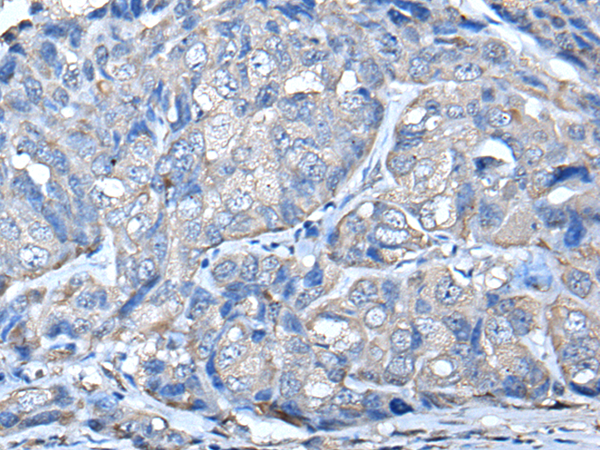

分类: 科研抗体货号: P01679别名: LPTP; HEPTP; PTPNI; BPTP-4; LC-PTP应用: WB,IHC反应种属: Human, Mouse, Rat